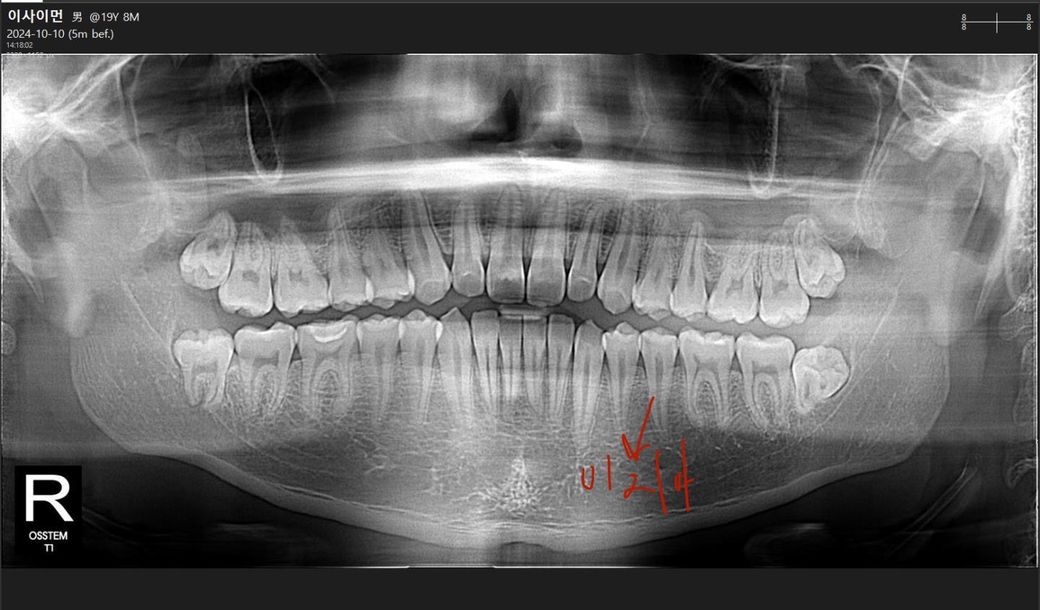

일단 깊은 충치는 아닌듯하고요

치근단병소(치아뿌리끝 염증)가 있었을지는 작은 엑스레이 사진이 짤려서 확인이 어렵습니다

사진으로만 보면 문제가 없어 보이긴 합니다. 저 사진만 보고 신경치료후에 씌워야 한다는 치료계획이 어떻게 나온건지는 모르겠는데요. 혹시 금이 갔다거나 사진상으로 안보이는 무언가가 있어서 그랬을 수는 있지만 아프지도 않았다고 하시니 어떤 것 때문에 하셨는지는 저로서는 잘 모르겠네요.

사진을 봤을 경우에는 인접면 충치가 있는것으로 보입니다.

엑스레이 상으로는 큰 문제가 없어 보이지만 금이 갓거나 그렇다면 크라운 치료가 필요한경우가 있습니다.